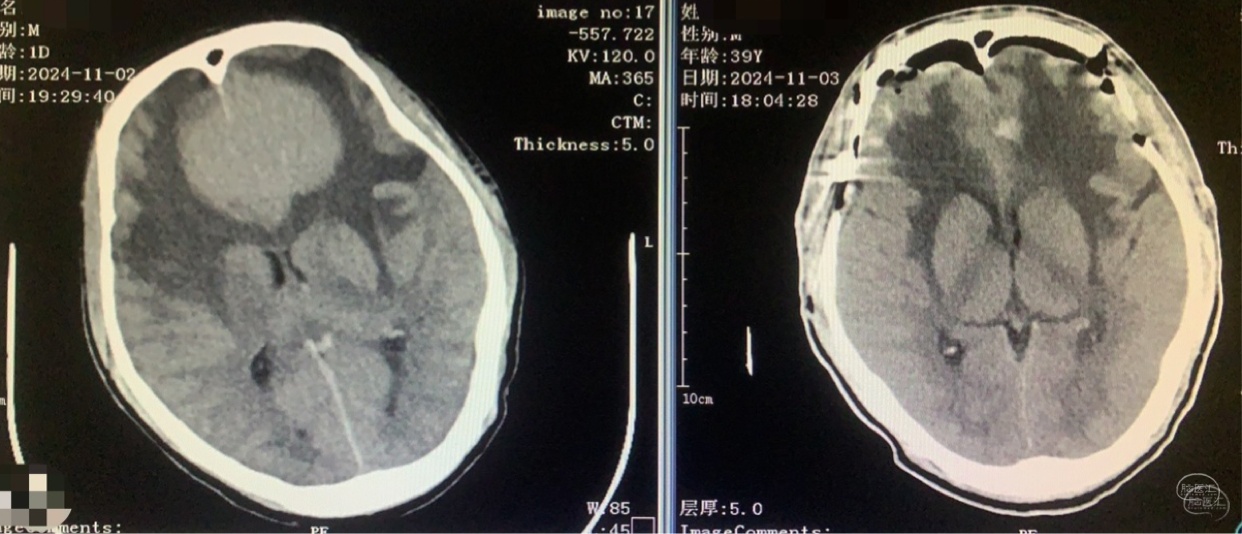

术前CT

术前术后对比